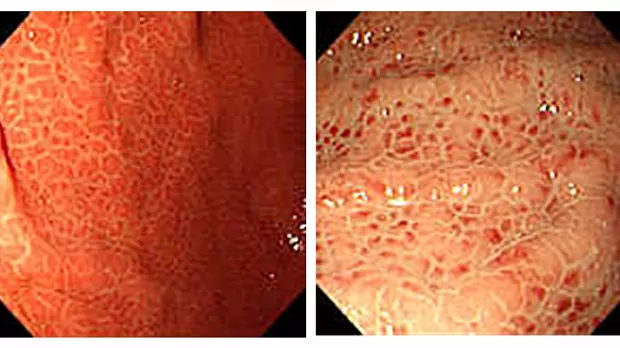

Для врача-эндоскописта очень важно определение эндоскопической картины неизмененной слизистой на уровне «узнавания». Это позволяет не только точно определить отсутствие патологии, но и выявить незнакомую патологию. Неизмененная слизистая желудка красновато-розовая, гладкая, блестящая, с равномерным распределением собирательных венул, признак имеет диагностическую ценность при определении по малой кривизне нижней трети тела желудка.

Эритематозная гастропатия – это покраснение слизистой оболочки желудка (СОЖ) в сочетании с усилением ее васкуляризации. Может быть очаговым (ограниченным) или диффузным (распространенным). Благодаря колоссальной распространенности этого, казалось бы, неспецифического симптома, сформировалось очень легкое отношение к нему среди как эндоскопистов, так и клиницистов. Некоторые из них считают его чуть ли не проявлением нормы. Однако, термин «эритематозная гастропатия» объединяет целый ряд состояний СОЖ, различных по своим визуальным и прогностическим признакам. На сегодняшний день публикуется достаточно много исследований, посвященных привязке тех или иных вариантов гастропатий к хеликобактер-ассоициированному гастриту. Рассмотрим формы эритематозных гастропатий. Диффузная эритема – это равномерное покраснение всей слизистой желудка, включая слизистую проксимальных отделов. Данные изменения патогномоничны для хеликобактер-ассоциированного гастрита (Нр+). Диффузная эритема может сочетаться с отеком (желудочные поля четко контурированы, слизистая утолщена, рисунок слизистой не изменен), что так же является маркером Нр+. Эритема диффузная или очаговая, может сочетаться с фолликулярной гиперплазией слизистой желудка: слизистая желудка (чаще антрального отдела) гиперемирована, зернистая. Зернистость обусловлена разрастанием лимфоидных фолликулов в собственной пластинке слизистой желудка. Зернистость слизистой антрального отдела желудка является единственным достоверным признаком Нр+. Стоит отметить, что подобным образом может проявляться MALT-лимфома желудка. Необходимо провести морфологическое исследование СОЖ, особенно в случаях обнаружения крупных или неравномерных узелков. И вообще следует всегда помнить, что лимфома желудка может скрываться за любыми макроскопическими изменениями СОЖ.